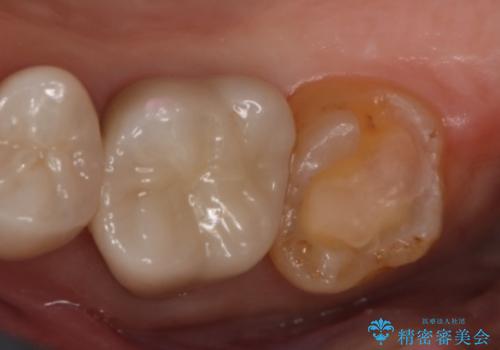

- 右上7番の銀歯のやりかえを主訴に来院された患者様です。

切削量・形態を考慮し、セラミックインレーでの治療を計画しました。